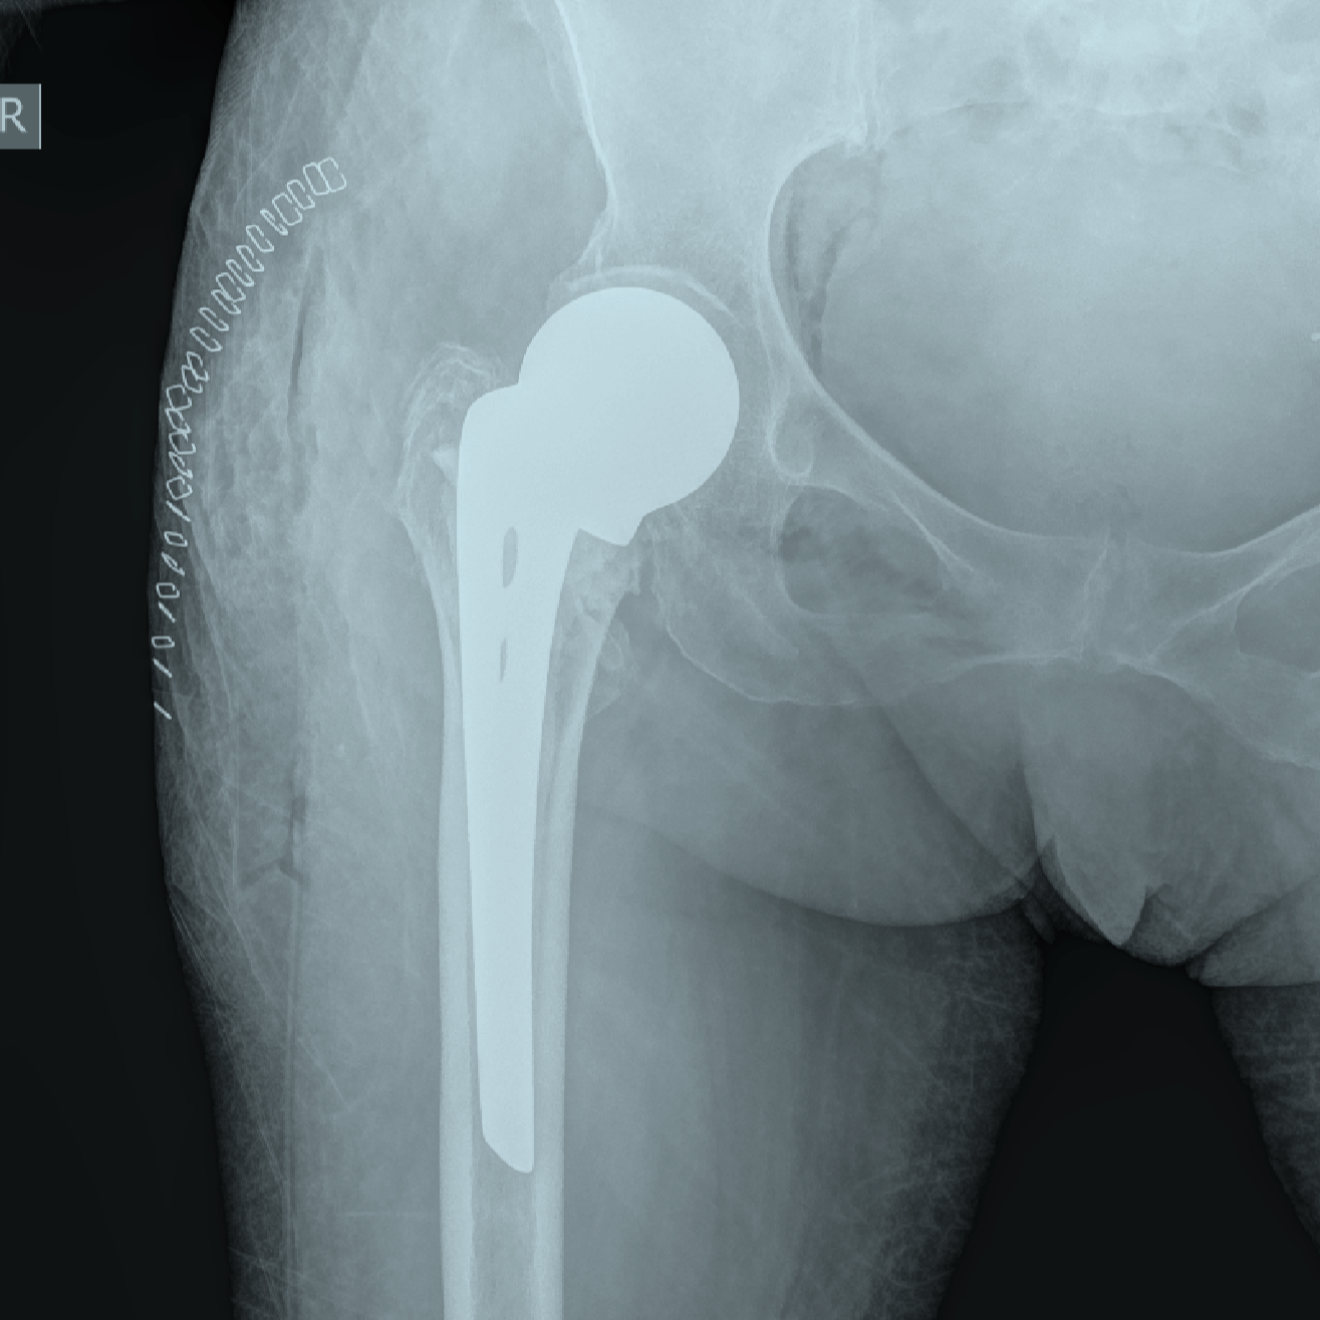

Radiografía de cadera con prótesis de reemplazo de cadera

Prótesis de cadera